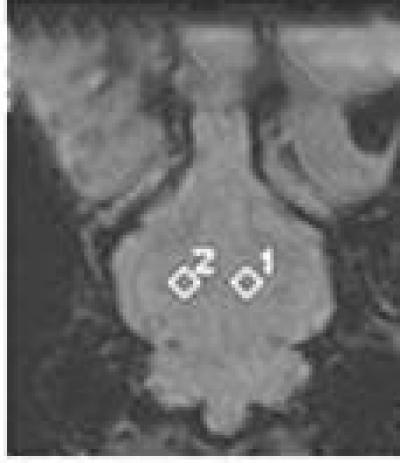

After the fifth bloodletting, the susceptibility-weighted imaging signal (diamonds 1 and 2) of the rabbit thalamus is significantly lower compared with pre-bleeding.

(Photo Credit: Neural Regeneration Research)